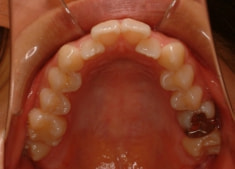

上顎前突+右下7番重度埋伏

(右下7番目の永久歯が下顎の中に埋まったまま、親知らずが上に乗っている)

治療法:フルパッシブブラケット:T21

解説:右下7番を抜歯し、右下8番を開窓牽引しました。近年、顎が退化しており、歯の大きさとの不調和がどんどん強くなりつつあります。2018年の矯正学会でも、本症例と同様の下顎7番8番の問題ケースが講演で紹介されておりました。こうなる前に、先手を打ちたいものです。小児の間に先行治療できるのがベストですので、お子様が6才になったら矯正専門医院に初診相談に行くようにしましょう。やる必要があるかどうかを聞きに行くのです。

治療前

治療後(2年3ヶ月後)